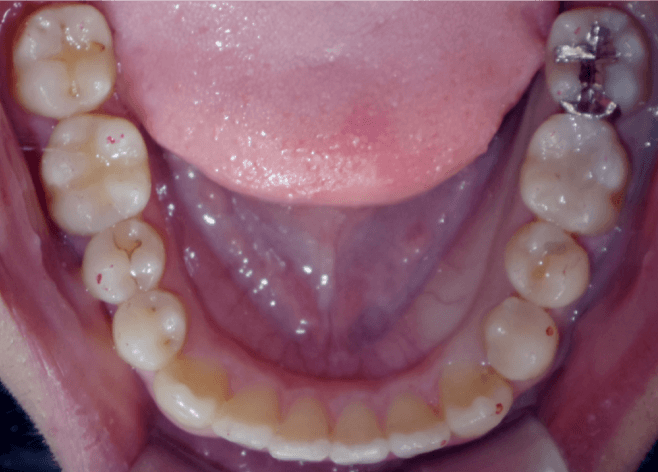

八重歯(重度叢生)

BEFORE

AFTER

担当医コメント

重度の叢生だが、患者の希望により非抜歯での治療を検討した。補綴が多いため補綴に対してのIPRでスペースを確保し、上顎大臼歯の遠心移動を組み合わせ治療することにした。上顎犬歯の歯肉退縮は患者の希望によりこのままで進める事にした。

年齢/性別

40歳 女性

主訴

噛み合わせ八重歯が気になる。上顎の歯が内側に入っているのが気になる

リスク

歯肉退縮が起こる可能性がある。

歯肉退縮を起こしている部位がより進行する可能性がある。

費用

85万円(矯正費用)

期間

2 6 ヶ月